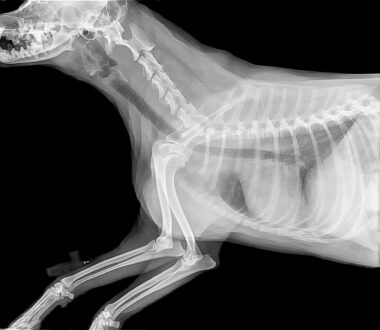

Seeking immediate veterinary care after a suspected fracture is vital for your pet’s health and recovery. Delaying treatment can increase the risk of complications significantly. Each day a fracture remains untreated could lead to further misalignment or complications such as infection. In addition to physical healing, addressing pain management with a veterinarian is essential. Pets can suffer significantly from pain due to broken bones, and pain relief should be a priority. Your veterinarian may prescribe medications to manage pain and ensure comfort during the healing process. Additionally, if you suspect a fracture, be cautious not to handle your pet too much, as this might increase discomfort. Veterinary diagnostics, including X-rays, will allow veterinarians to ascertain the nature of the fracture and make informed recommendations for treatment. Following a clear treatment protocol will aid your pet in recovery, allowing for gradual rehabilitation as their condition improves. Overall, quick action can save your pet from extended pain and suffering, underscoring the importance of proactive care whenever injury occurs.